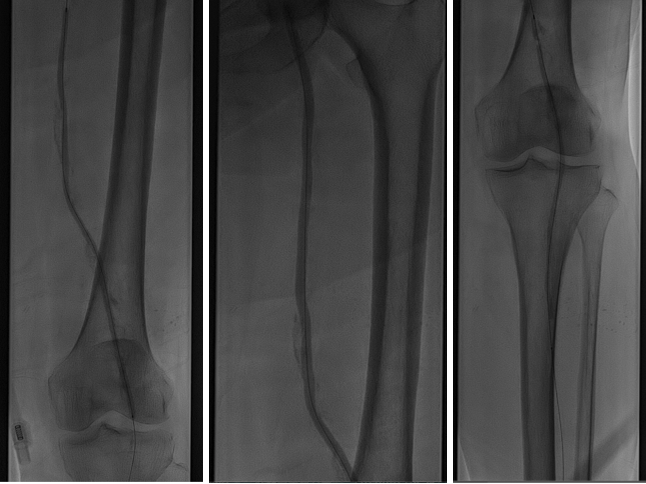

图:推送saber球囊

图:开通腘动脉主干

图:4mm/5mm球囊顺序行股腘动脉PTA,3mm球囊行腓动脉PTA

图:由肱动脉先行股动脉支架置入,而后顺行穿刺股总动脉

图:胫腓干夹层,置入3.5mm*35mm药涂支架(冠脉支架)

图:术后造影示股腘动脉、腓动脉及足部动脉显影好